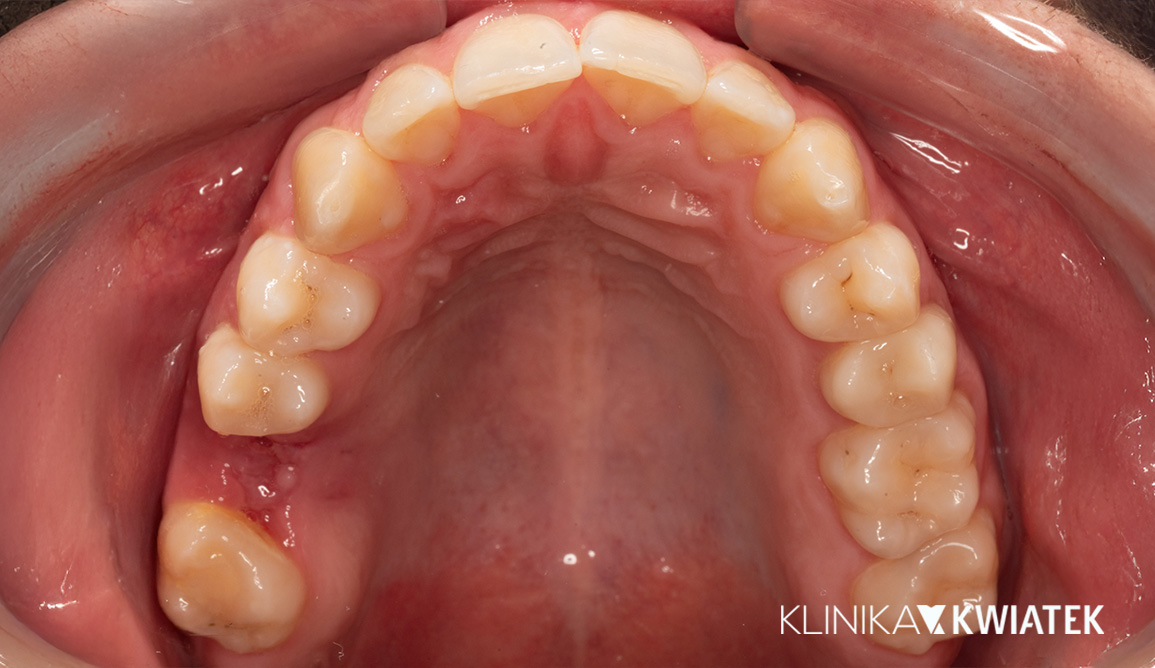

Kliniczna precyzja i estetyka – jak przywróciliśmy funkcję i piękno uśmiechu

Pacjentka zgłosiła się z wadą zgryzu, licznymi ubytkami i utraconymi zębami trzonowymi, co powodowało trudności w żuciu i estetyczne niezadowolenie. Leczenie obejmowało ekstrakcje, ortodoncję, implantację oraz kompleksową rekonstrukcję protetyczną. Po kilkunastu miesiącach terapii Pacjentka odzyskała pełną funkcję zgryzu i piękny, harmonijny uśmiech.